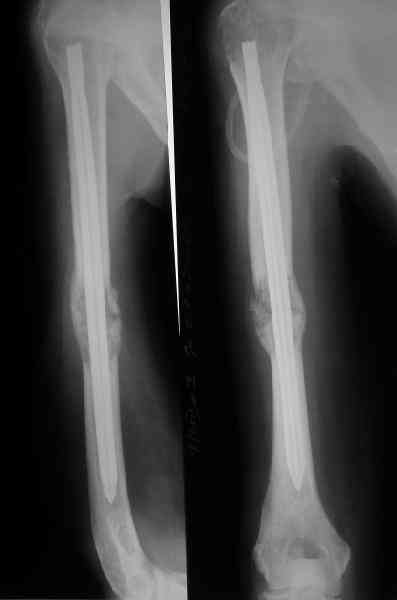

Женщина 53 лет получила патологический перелом правого плеча в феварле, и левого в марте - mts из невыясненного первичного очага.

Сегодня сделали, Fixion диаметром 7,4 мм. Обе пперации продолжались по 7 мин. Картинки в приложении. Наркоз был диприваном, на спонтанном дыхании. По крайней мере, пока довольны хотя бы анестезиологи, похоже, не верили, что управимся меньше, чем за час ;-)

Гвоздик 7,4 расширяется до 11 мм. Не маловато ли, судя по снимкам?